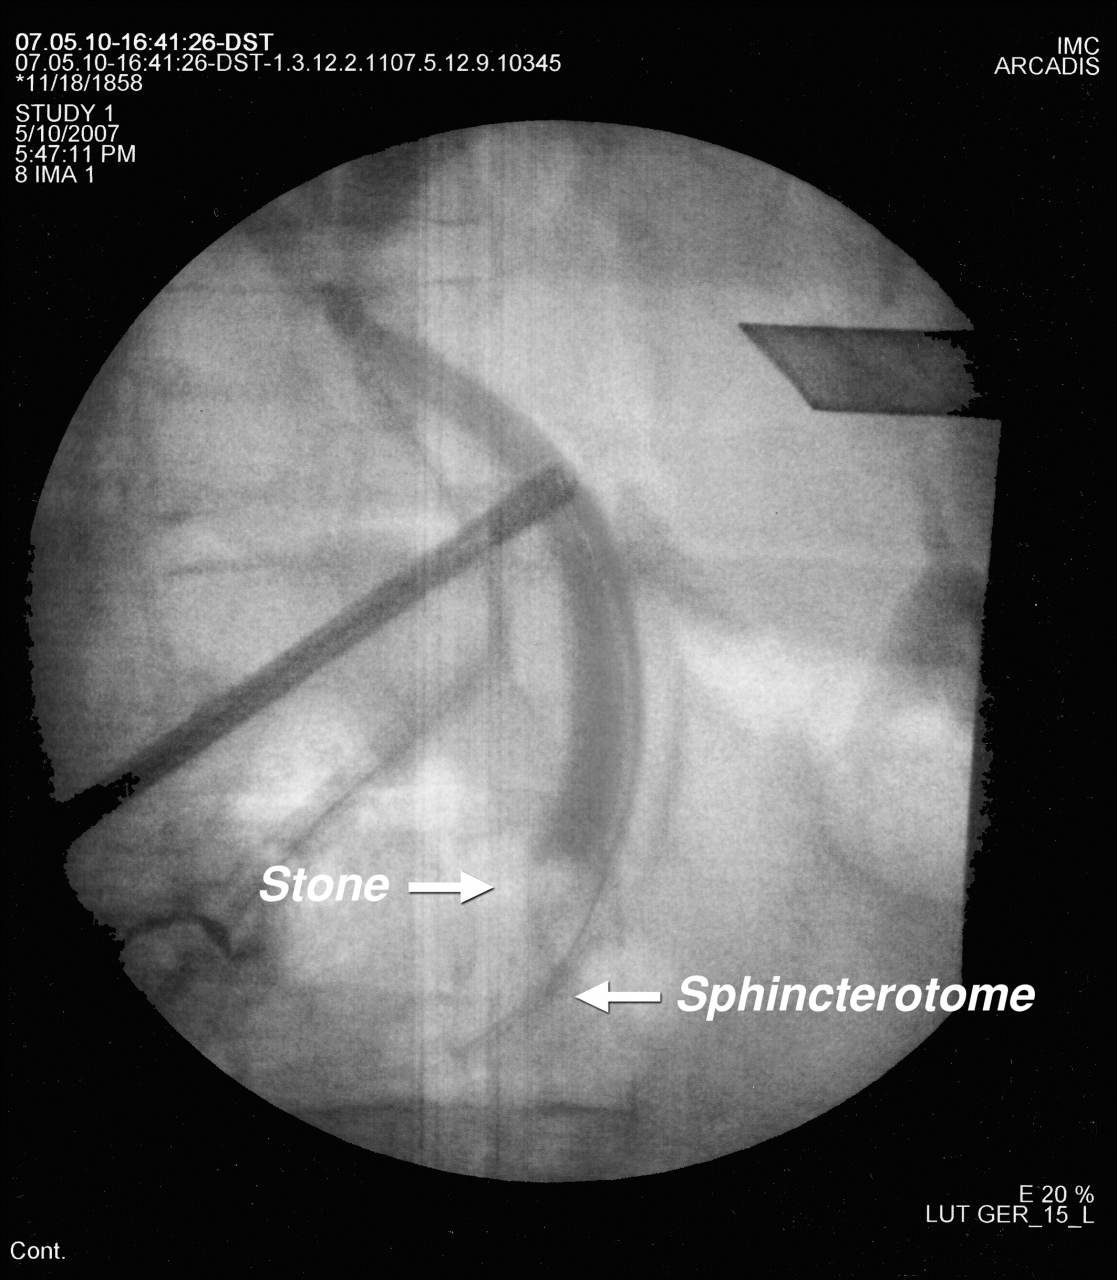

ERCP işlemi en sık safra kanalı (koledok) taşlarının tanı ve tedavisi için yapılır. Safra kesesi taşı + safra kanalı taşları birlikte olduğunda değişik tedavi seçenekleri vardır. 1) Önce ERCP sonra kolesistektomi (safra kesesinin alınması), 2) kombine işlem: kolesistektomi ve ERCP aynı seansda yapılması 3) önce safra kesesi alınır takibinde ERCP ile kanal taşları temizlenir. Günümüzde en sık kullanılan yöntem önce ERCP ile kanal taşlarının alınması ve takibinde kolesistektomi yapılmasıdır. Ancak cerrahların ERCP yapması ve teknolojide meydana gelen hızlı gelişmeler tek aşamalı işlemin (laparoskopik kolesistektomi + ERCP) giderek daha popülarite kazanmasına neden olmuştur2. Tek aşamalı işlemin diğer yöntemlere göre önemli üstünlükleri vardır2,3.

Yukarıda belirtilen avantajlarından dolayı biz safra kesesi taşı + safra kanalı taşı olan hastalarda tek seanslı işlemi (lap. Kolesistektomi +ERCP) tercih etmekteyiz. 2000 yılından itibaren uyguladığımız tek seans kombine işlem tekniğinde aldığımız sonuçlar mükemmeldir2,3.

Tek aşamalı işlemin şematik görünümü

Tek aşamalı işlemin radyolojik görünümü